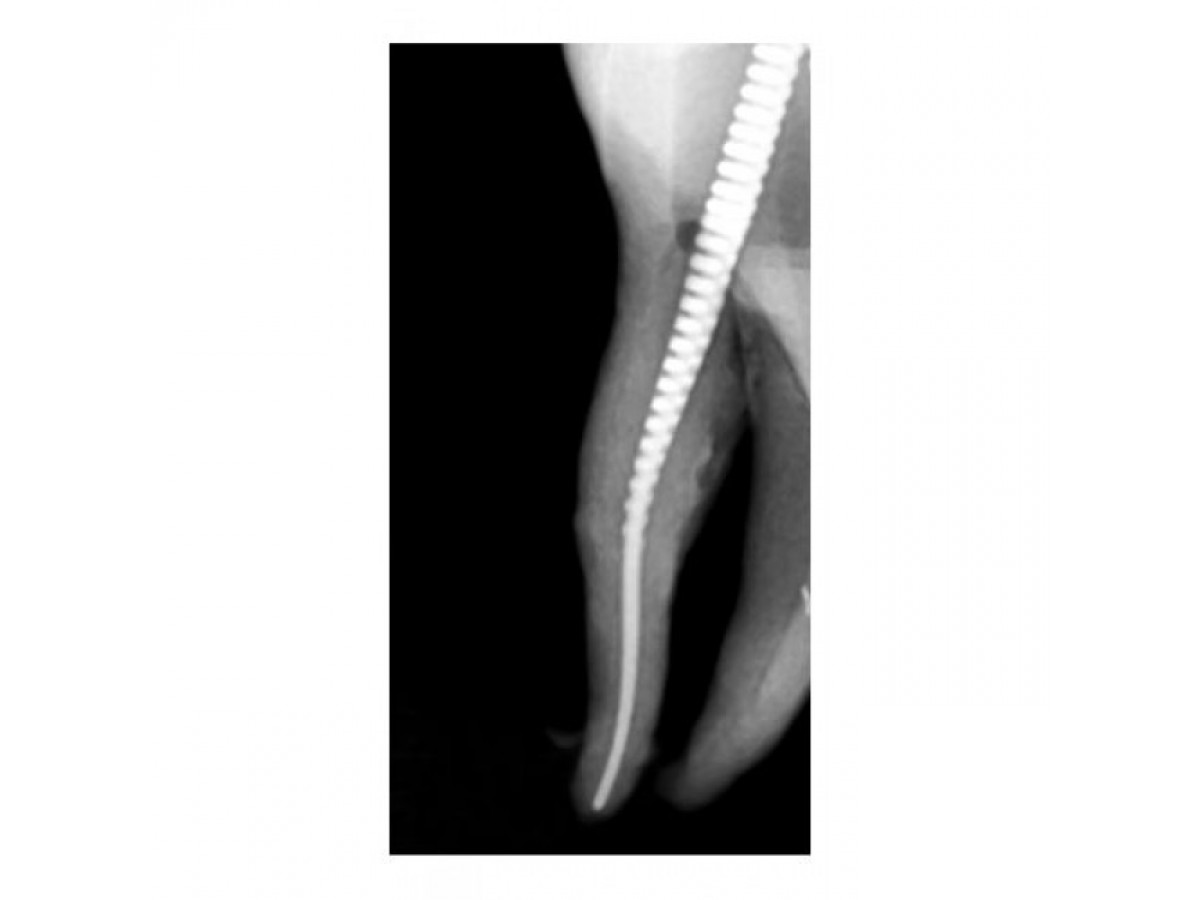

- Благодаря шершавой поверхности и высокой скорости вращения, Gentlefile шлифует стенки корневого канала, а не сверлит и не режет дентин, как это делают NiTi-файлы.

- Кончик файла пассивен – он гладкий и без острых граней. Такой дизайн позволяет файлу продвигаться по каналу в соответствии с анатомическим строением и предотвращает случаи перфорации.

- Горизонтальная сила (между файлом и стенками канала) и вертикальная сила (позволяющая файлу продвигаться) уравновешены, из-за этого сохраняется естественная анатомия канала.

- Вращаясь со скоростью 6500 об/мин. файл разбрасывается центробежной силой - за счет чего обрабатываются стенки каналов любой формы в горизонтальной плоскости.